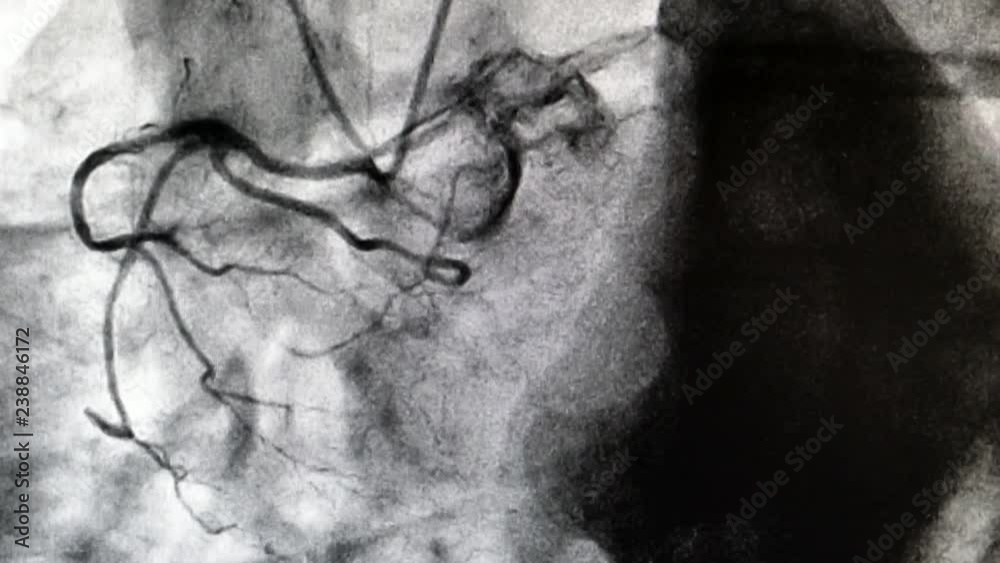

Cardiac Catheterization Via the Right Radial Artery With a Judkins Left Catheters Used For Left Ventriculography Include left ventriculography technique and indications in random case. Perform left ventriculography with a multisidehole catheter using a power injector. This widely used method requires separate preformed catheters for the right and left coronary arteries (see the images below). Correlation of the findings from coronary angiography with those from left ventriculography permits identification of potentially viable areas of the myocardium. Catheters Used For Left Ventriculography.